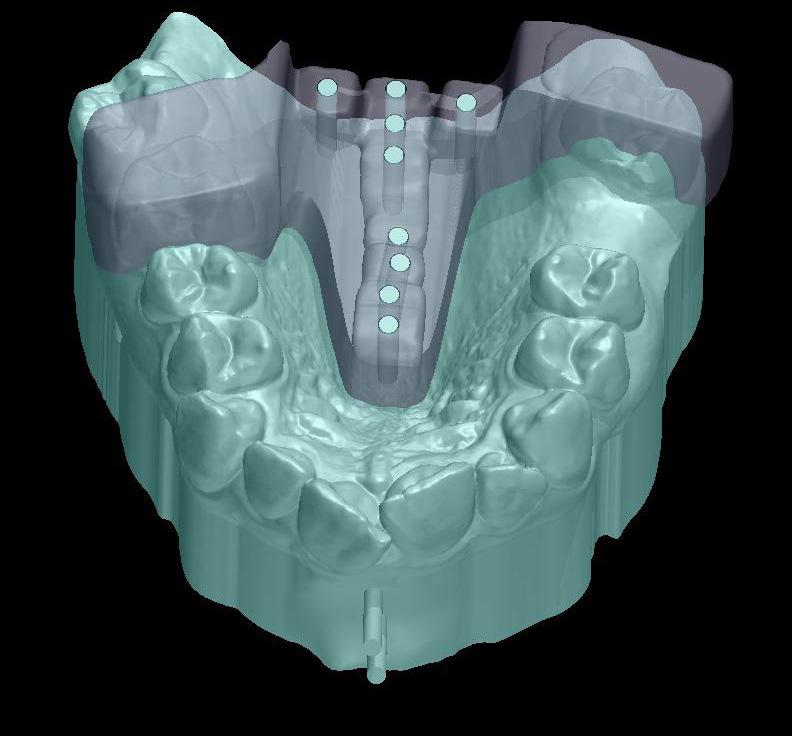

Standard orthodontic pretreatment records (T0) were obtained (Figure 1). The same operator obtained the lateral cephalogram and OPG using the same machine. The lateral cephalograms were traced manually with the standard technique by a single

investigator and a total of 06 skeletal, 11 dental, and 03 soft tissue parameters were measured. Selected patients were also subjected to Acoustic pharyngometry (AP) for a three-dimensional evaluation of the upper airway. Fixed orthodontic appliance (022” MBT PEA) was bonded on both maxillary and mandibular arch, with banding of first & second molars. A standard wire sequence was followed till the full slot engagement with SS wire (19 X 25”) was achieved. A complete set of records were made to register the beginning of the fixed functional phase (T1) (Figure 2). Forsus appliance (FFRD) was fitted for each patient, push rod hooked on the archwire between canine and 1st premolar in the maxillary arch and distal end of open coil spring connected with the ‘L’ pin to the 1st mandibular molar. Maxillary and mandibular components of the Forsus FRD were connected to provide a forward thrush to the maxilla and a backward thrust to the mandible during the closure of the mouth (Figure 3). The functional phase with Forsus FRD continued till the desired objectives were achieved i.e., achieving positive overjet as well as satisfactory improvement in soft tissue profile.